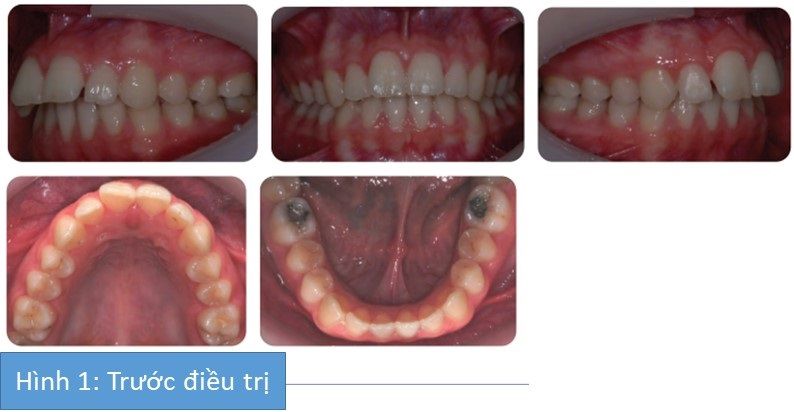

Bệnh nhân nữ 16 tuổi có sai khớp cắn hạng II trên nền xương hạng II trung bình với kích thước dọc trung bình, phức tạp do mút môi và độ cắn chìa lớn.

Bệnh nguyên của cắn chìa tăng là gì?

- Hàm dưới lùi sau

- Mút môi

- Các răng cửa hàm trên nhô ra trước